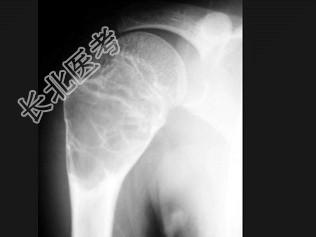

- 单项选择题男,15岁, 右肩疼痛1月余,结合图像, 最可能的诊断是 ( )

A、嗜酸性肉芽肿

B、动脉瘤样骨性囊肿

C、骨样骨瘤

D、血管瘤

E、以上都不是